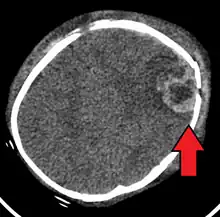

| An intraparenchymal bleed with overlying skull fracture from shaken baby syndrome | |

A skull fracture from abusive head trauma in an infant